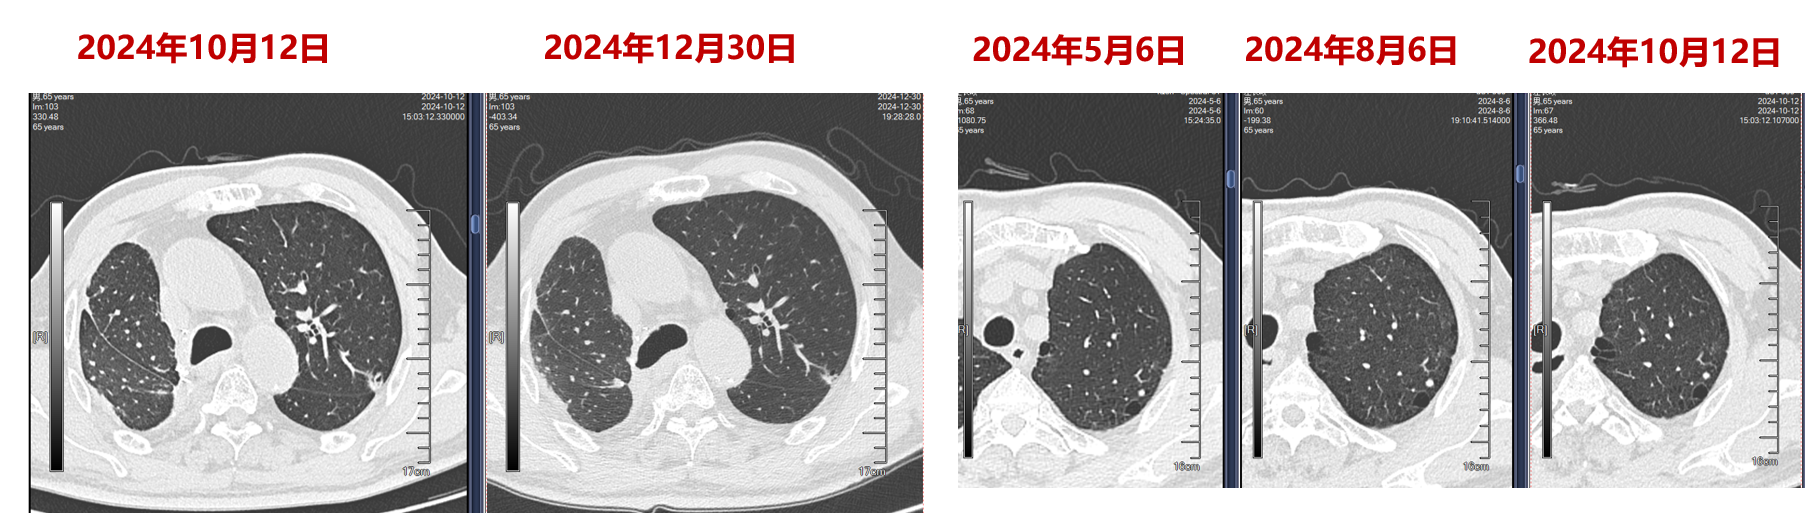

辅助放疗:鉴于治疗前影像提示病灶侵犯胸壁及肋骨,术后于2024年7月4日启动针对胸壁及瘤床的辅助放疗(PTV 4Gy13f)。

免疫维持:2024年8月起,启动纳武利尤单抗单药维持治疗(1次/月)。

病情监测与局部强化:2025年5月复查提示左肺病灶较前增大,虽然病理活检提示炎症可能,但考虑到肿瘤风险,于2025年8月28日行冷冻消融处理,并继续维持免疫治疗,目前随访病情稳定。